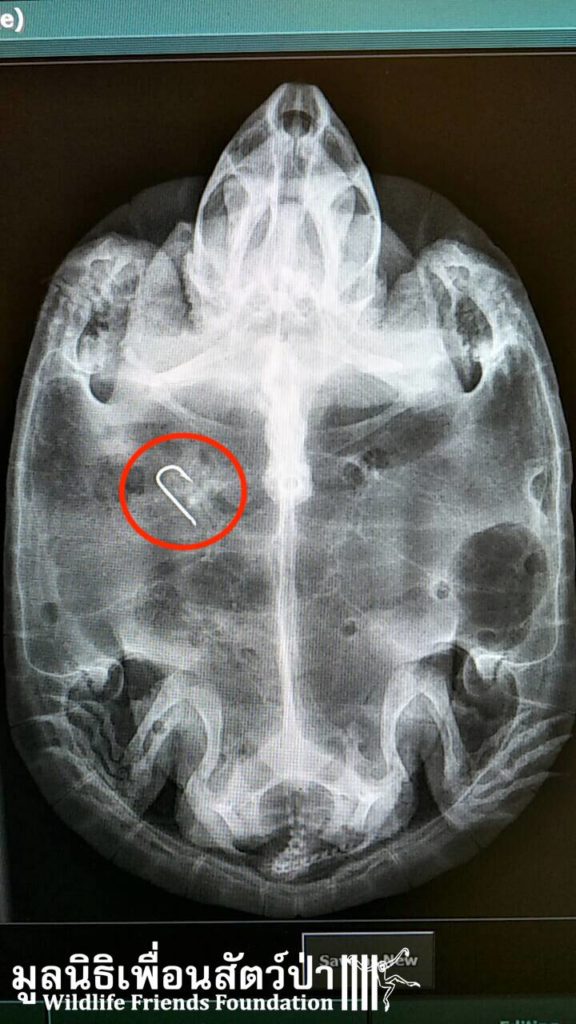

Last week we rescued numerous turtles from a temple in Rayong, see the rescue story here https://bit.ly/2nFimsp. They had been dumped at the temple over a period of years, sadly their living conditions were terrible, with green stagnant water, nothing to hide under and a diet of boiled rice. These poor little critters were dying due to bad diet and bad hygiene. We had to build a new special area to provide the suitable care to these animals, heat lamps and swimming pools have been installed in their new sandy enclosures. The WFFT Vet Team have been performing full health checks on all the turtles, including x-ray. We found fishing hooks inside 3 of the turtles, sadly one did not make it. For now, the other 63 turtles are doing well and enjoying their new clean home with clean water and fresh food. Once they have gone through a quarantine period they will be returned back to the wild. We will keep you posted.